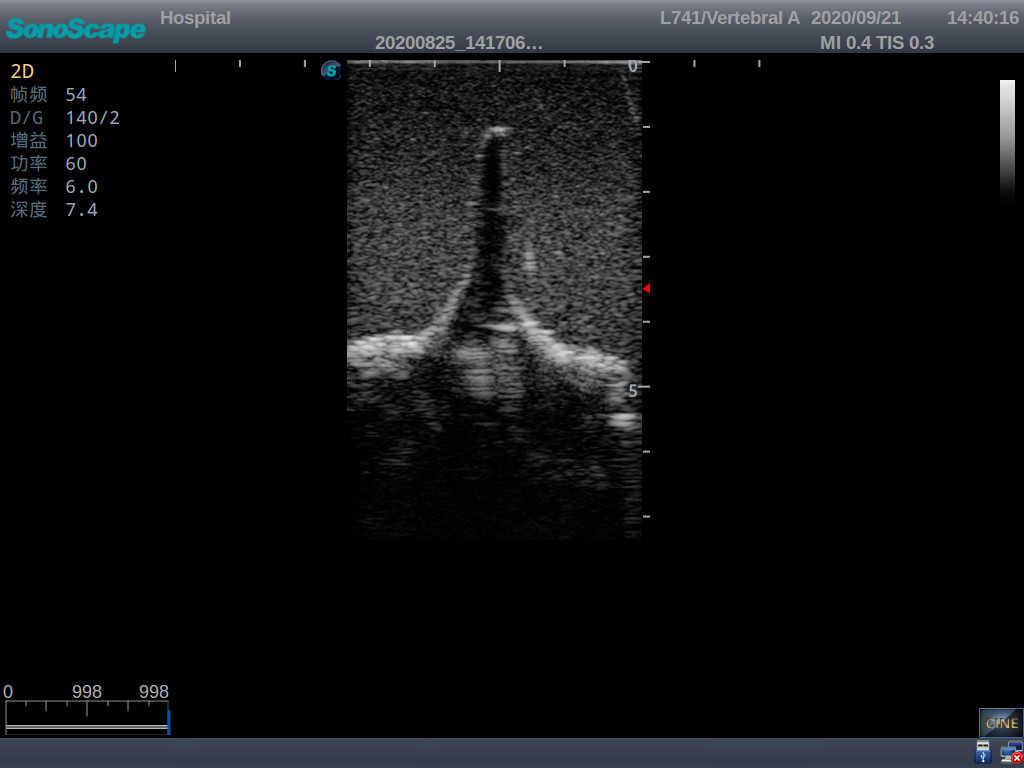

Adult Lumbar Puncture Ultrasound Training Model

Model TYE1549.2

This model is an ideal choice for ultrasound-guided adult lumbar puncture training with true-to-life skin feel and touch, accurate anatomical structures as well as real clinical ultrasound images. Realistic resistance to needle tips and correct landmarks provide excellent hands-on experience.

Accurate anatomical structure of L1-L5 and the vertebral canal

2)  Real clinical ultrasound images

3)  Compatible with various real ultrasound machines

1)   Ultrasound-guided lumbar puncture practice